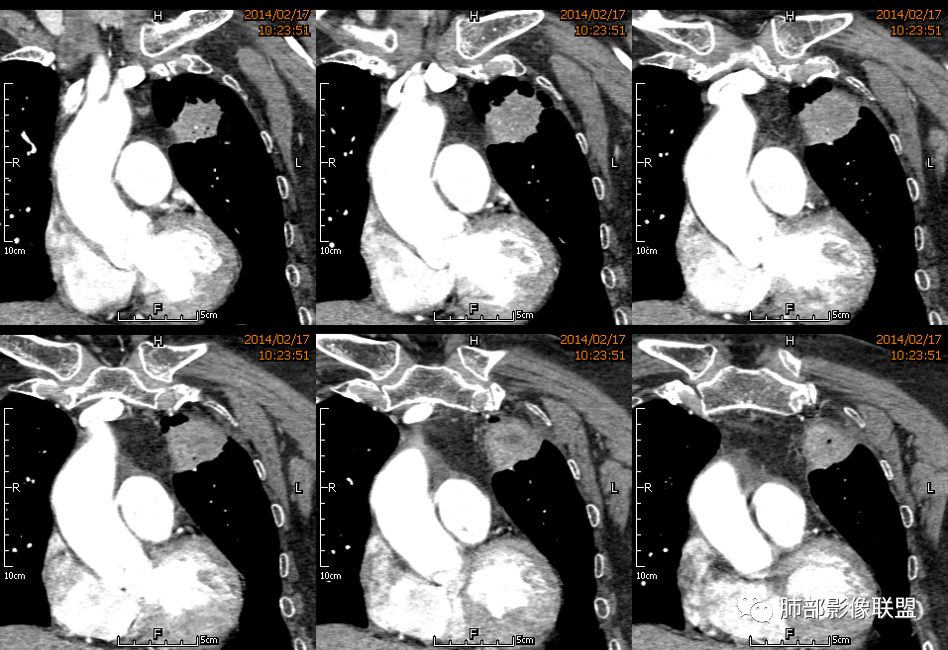

3.病灶密度不均,中央坏死液化并见气泡影,支气管及血管贴边进入,较均匀环形强化(显示多层结构),未见明确壁结节。

3.病灶易坏死液化,环形强化,支气管及血管贴边进入,“火焰”样边缘轮廓,更符合炎性块影的特点。